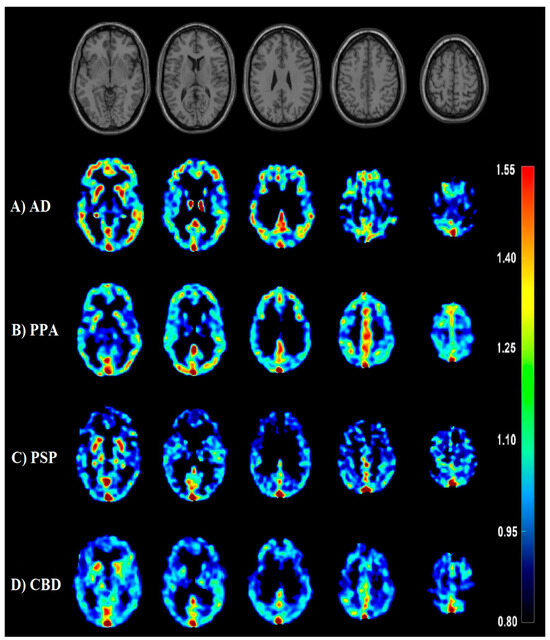

- Minoshima, S.; Cross, D.; Thientunyakit, T.; Foster, N.L.; Drzezga, A. 18F-FDG PET Imaging in Neurodegenerative Dementing Disorders: Insights into Subtype Classification, Emerging Disease Categories, and Mixed Dementia with Copathologies. J. Nucl. Med. 2022, 63, 2S–12S. [Google Scholar] [CrossRef]

- Nestor, P.J.; Altomare, D.; Festari, C.; Drzezga, A.; Rivolta, J.; Walker, Z.; Bouwman, F.; Orini, S.; Law, I.; Agosta, F.; et al. Clinical utility of FDG-PET for the differential diagnosis among the main forms of dementia. Eur. J. Nucl. Med. Mol. Imaging 2018, 45, 1509–1525. [Google Scholar] [CrossRef]

- Jang, Y.K.; Lyoo, C.H.; Park, S.; Oh, S.J.; Cho, H.; Oh, M.; Ryu, Y.H.; Choi, J.Y.; Rabinovici, G.D.; Kim, H.J.; et al. Head to head comparison of [18F] AV-1451 and [18F] THK5351 for tau imaging in Alzheimer’s disease and frontotemporal dementia. Eur. J. Nucl. Med. Mol. Imaging 2018, 45, 432–442. [Google Scholar] [CrossRef] [PubMed]